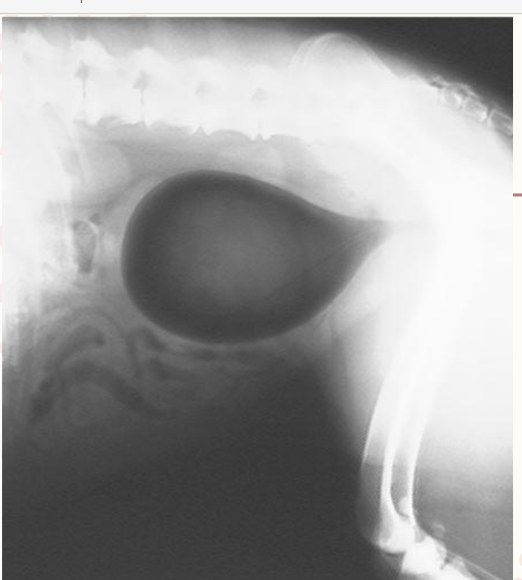

Double contrast, what is it?

A radiographic contrast technique that uses a combination of both positive & negative-contrast media simultaneously.